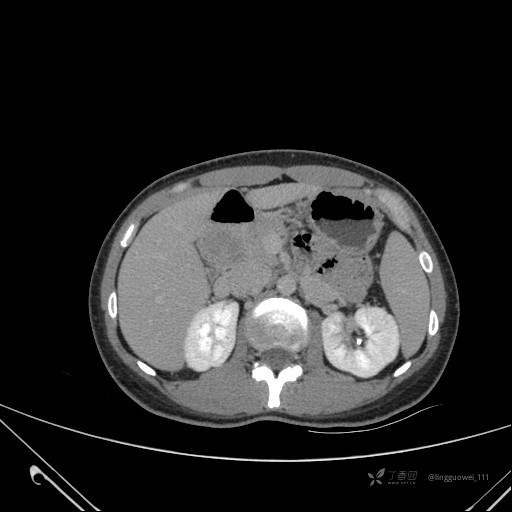

患者性别:女

患者年龄:28岁

主诉:体检发现胰腺病变,行 CT检查。

平扫:

动脉期:

门脉期:

延迟期: